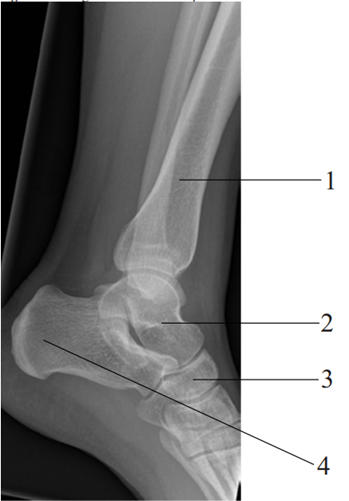

Em relação à anatomia radiográfica do tornozelo, marque a alternativa que corresponda aos pontos indicados na radiografia em perfil

do tornozelo.

Figura 01 -Imagem do tornozelo em perfil

Fonte: NETO et al.(2022, p.67) / Francisco Abaeté Neto; Leonardo M. Lustosa; João Erivan Façanha Barreto. Atlas radiográfico ilustrado: ossos e articulações [recurso eletrônico]. Fortaleza: Editora Caminhar, 2022. Pag. 67.